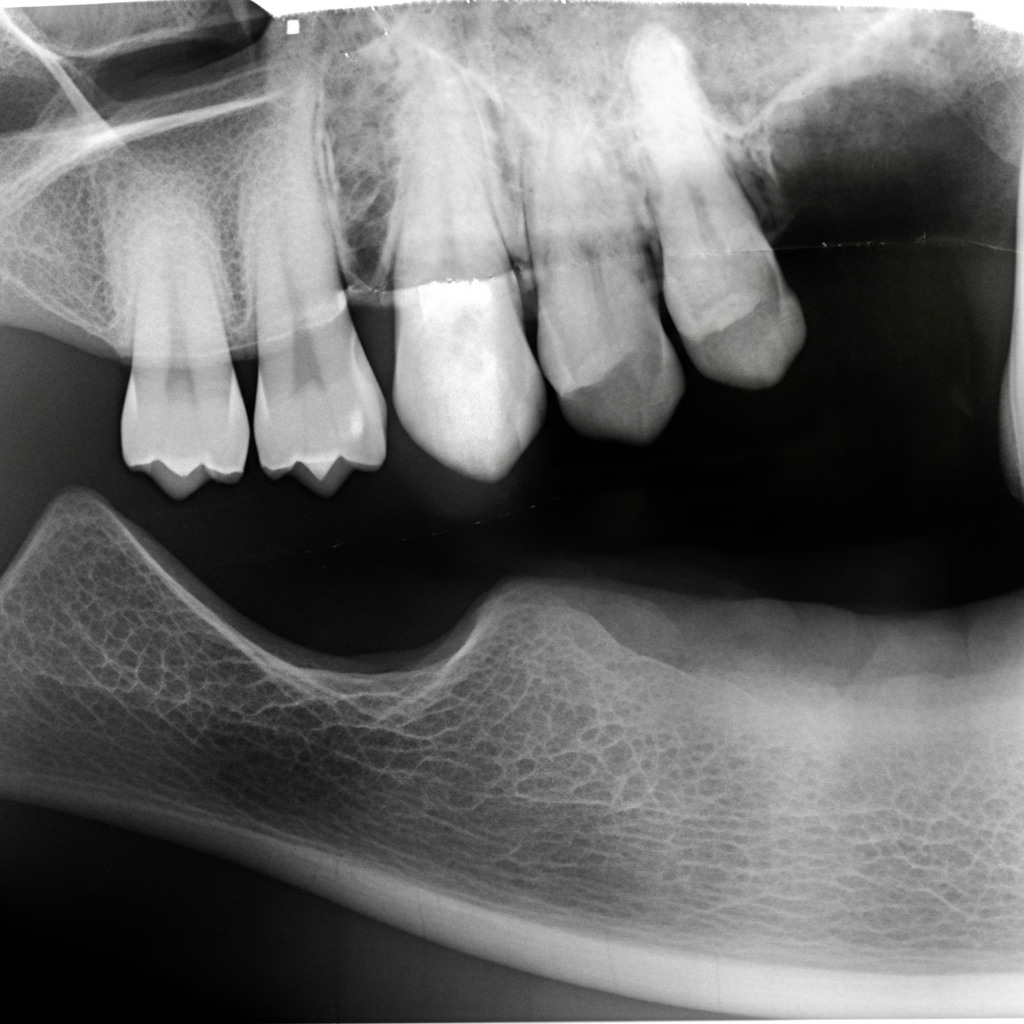

Diagram showing the first stages of the closure of an OAF using a Palatal Rotation Flap.

In this case, the antral polyp & the OAF is excised.

An alveoplasty also aims to facilitate the healing procedure as well as the successful placement of a future prosthetic restoration.